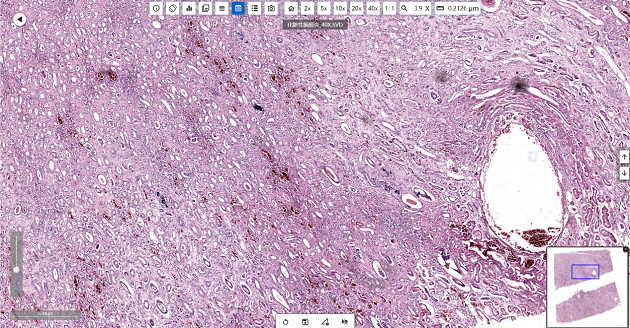

In addressing emerging infectious diseases, chronic diseases and global public health challenges, pathology laboratories of the Centers for Disease Control and Prevention (CDC) undertake critical tasks including disease diagnosis, pathogen identification and source tracing of public health incidents.

As fundamental equipment in the laboratory, optical microscopes play an irreplaceable role in histopathological analysis, pathogen detection and mechanistic studies.

Optical microscopes are involved in the entire workflow of disease diagnosis, mechanistic research, and public health decision-making in pathology laboratories of the Centers for Disease Control and Prevention (CDC).